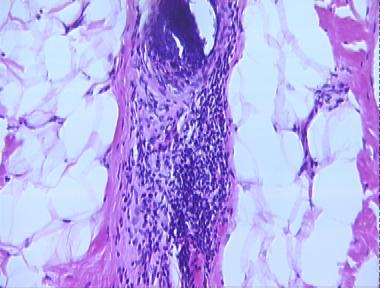

alopecia areata

Histologic Features